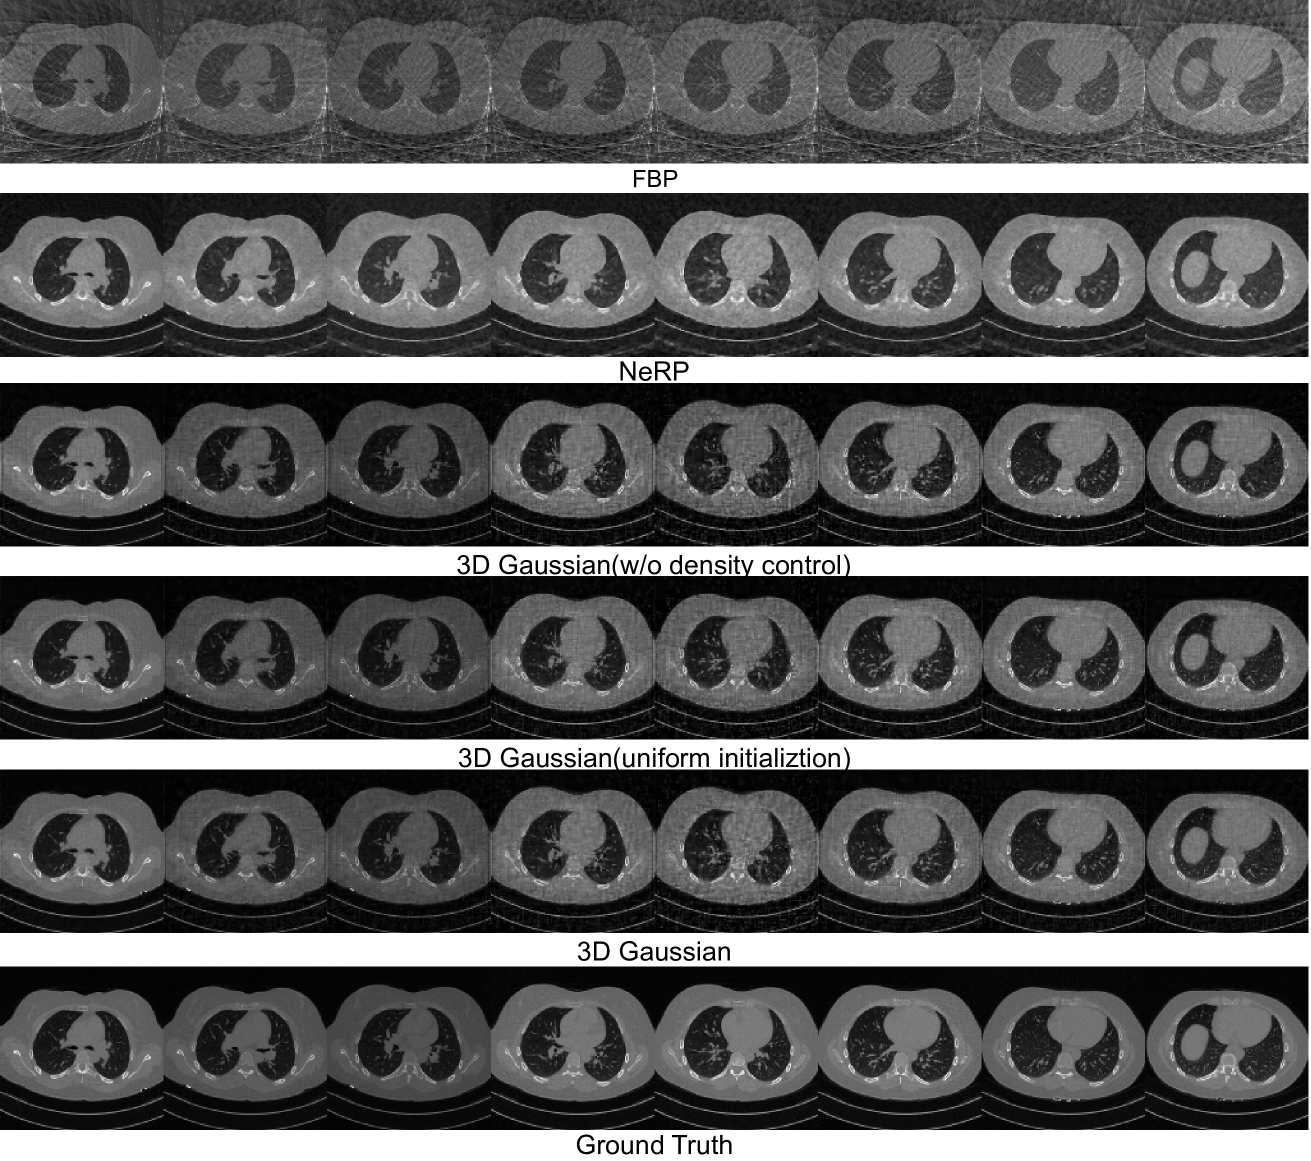

Quantitative results are provided in Table 1, 3D Gaussian achieves superior performance in most cases, usually by a large margin. A visual comparison between images reconstructed using NeRP and 3D Gaussians is shown in Fig. 3. Compared to NeRP, reconstructing images with 3D Gaussians provides cleaner results in empty regions and better high-frequency details like the airways.

We further explore factors that affect the reconstruction quality with 3D Gaussians. This includes examining the number of Gaussians involved and their initialization method, as well as providing evidence of the efficacy of adaptive density control.

To understand the number of Gaussians needed to represent an image volume, we turn off the adaptive density control during training, which brings perturbation to the number of Gaussians, and use 10K, 50K, 150K, 300K, 400K, 600K Gaussians to represent a volume. The results are shown in Fig. 3(b) and Fig. 3(c), respectively. The reconstruction performance generally improves with the increase in number of Gaussians used. However, an overly large number of Gaussians can lead to a degraded quality, which may be attributed to the low quality of initialized centers with the increase in number of selected points.

3.3.2 Initialization of Gaussians

We compare our initialization from FBP-reconstructed image strategy with uniform initialization. For uniform initialization, we use the same threshold to filter the air region and initialize the center of Gaussians uniformly across the foreground region, and all Gaussisans are initialized with the same standard deviation and intensity. Quantitative results are listed in Table 1, and visualization is provided in Fig. 3. Initialization from FBP-reconstructed images consistently outperforms uniform initialization by a large margin, suggesting the importance of starting with an informed initial placement of Gaussians.

3.3.3 Effectiveness of Adaptive density control

In our main experiment, we initialize an image with 150K Gaussians and set the upper bound to 400K. Comparisons of reconstruction with and without adaptive density control are provided in Fig. 3(b) and Fig. 3(c). Adaptive density control greatly improves the final reconstruction performance. Moreover, analyzing the correlation between number of Gaussians employed and reconstruction quality reveals that each substantial increase in number of Gaussians corresponds to a temporary drop in reconstruction quality, then recovery and improvement, as depicted in Fig. 3(a). This suggests adaptive density control helps place the Gaussians in a better place compared with solely based on optimization.